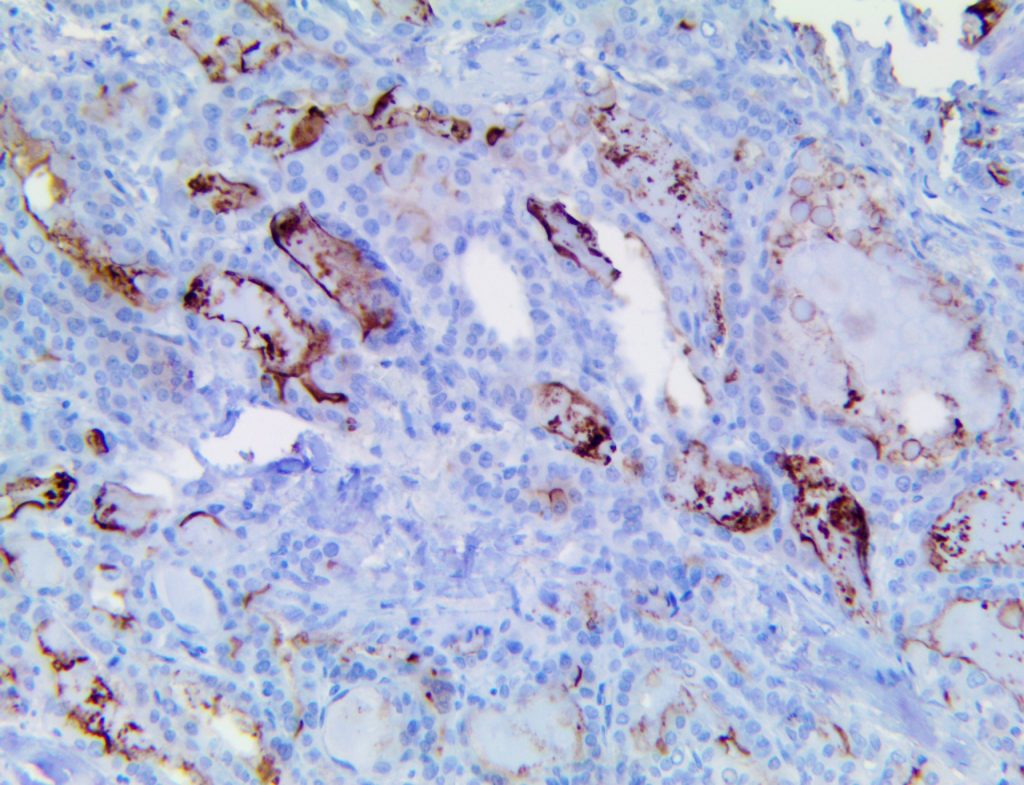

This activation induces inflammatory monocytes to highly express IL-6, starting a localized and then systemic cascade effect that results in hyperproduction of IL-6, which accelerates the inflammatory process. Because IL-6 also increases vascular permeability, excessive levels cause blood vessels to become very leaky. This, along with clotting factors released from vascular endothelial cells, stimulates the coagulation cascade, resulting in microthrombosis (tiny clots), which leads to ischemia and tissue death of the kidney, intestines, heart, liver, brain and extremities.